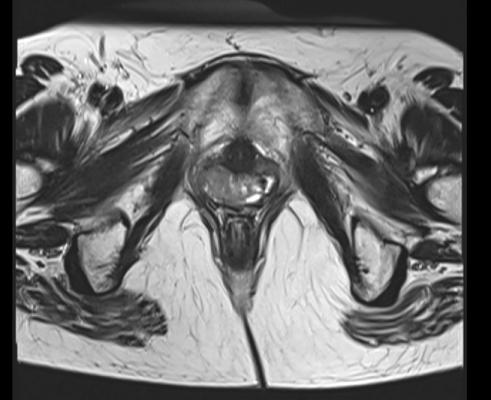

Advances in brachytherapy, such as the use of MRI imaging to pinpoint tumor size and location, along with the ability to deliver precise doses of radiation, have greatly improved tumor control and cure rates in recent years. The five-year survival rate for people with locally advanced cervical cancer is 74%.

Delivering high doses of radiation to tumors near the vagina, however, can lead to vaginal stenosis – a shortening or narrowing of the vagina – and long-term changes in vaginal tissue that can complicate gynecological examinations or cause pain during intercourse. Physicians often recommend regular and ongoing vaginal dilation to mitigate these side effects and prevent scar tissue from forming, but few studies have quantified its impact.